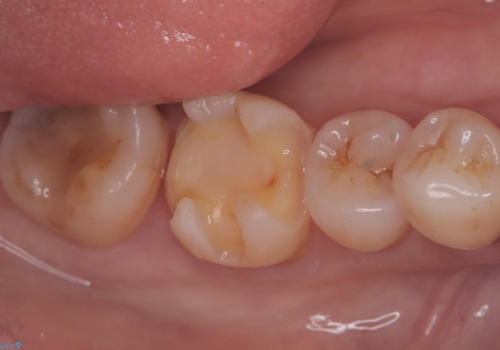

- 主訴:右下6番目と7番目の歯の間に食べかすがしょっちゅう詰まる

歯間に食渣がつまるのをどうにかしたいとの主訴のもと、治療を開始しました。フロスを通してみると、コンタクトは無く0.25mm程のスペースがありました。

メタルインレーを歯冠色のものに変えたいという希望もあったため、セラミックインレーでのやり替えによるコンタクトの再現をしています。